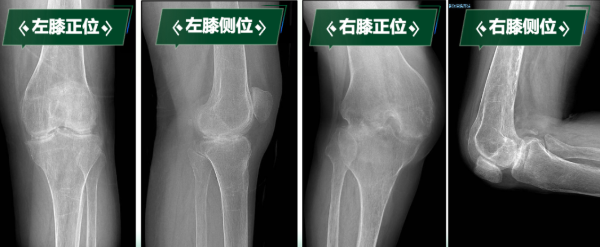

阳光讯(记者 郑亚雷)“真不敢相信,我能站起来,还能走路……”刘阿姨因罹患类风湿性关节炎多年,骨质受到严重侵蚀,导致双膝关节逐渐纤维性强直,更加棘手的是,双膝强直于两个极端体位,左膝关节无法弯曲,像“木棍”一样始终处于伸直状态;右膝长期处于极重度屈曲挛缩90度无法伸直。 这种“一伸一屈”的特殊畸形,导致无法正常坐立、行走,生活无法自理,身心承受巨大痛苦……

类风湿性关节炎整体发病率0.5~1%,约有10-20%会出现关节强直,关节致残率高达43.48%。“临床上一般超过30度的屈曲挛缩畸形定义为重度屈曲挛缩畸形,这种超过90度极重度屈曲挛缩非常少见,再加上‘一曲一伸’两种极端位置的强直,集中在同一个病人身上,手术难度和风险会成倍增加。”曹晓瑞副主任医师讲到。

下肢处于功能“锁死”状态的刘阿姨,不仅被剥夺了行走能力,还导致严重肌肉萎缩、骨质疏松,生活质量急剧下降,手术是帮助她重新站起来的唯一途径。科室高度重视,经多学科会诊讨论,制定周密治疗规划。曹晓瑞副主任医师团队分析术前影像学资料,精确评估膝关节骨质破坏、关节融合及周围软组织条件。

手术关键难点在于精准截除融合骨组织、获得屈伸间隙平衡、恢复下肢力线、确保韧带平衡以重建膝关节功能。团队凭借丰富经验和娴熟技术,成功实施双侧人工全膝关节置换术。术后影像学检查显示,假体位置精准,下肢力线完美纠正,原本僵硬关节被活动自如的人工关节取代,患者功能恢复理想,能正常行走,生活质量显著改善。